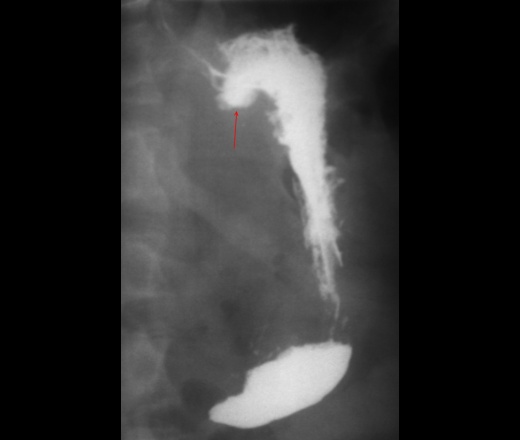

Мужчина 1950 г.р. в анамнезе в 2002 г. ушивание прободной язвы в в/3 задней стенки желудка. Жалоб по поводу желудка не предъявляет. Направили его ко мне с дивертикулом Ценкера (его я тоже за одно выложу). Вопрос: не может ли быть это (показано стрелками) крупным дивертикулом образовавшимся вследствии ослаблания мышечного слоя с пролябированием слизистой после операции.

Каскадный желудок более вероятен. Боковая проекция?

Нет это не дивертикул и не каскад. Вы сделали снимок после первых глотков, такое бывает у астеников. Боковой и косые снимки нужны.

+1. Я вот на каскад похоже. Для уточнения нужен снимок в боковой проеции. Можете ( хотя бы для себя, пересмортеть желудок), но скорее всего ваши подозрения, в плане дивертикула желудка, не подтвердятся.

вполне может быть передний каскад